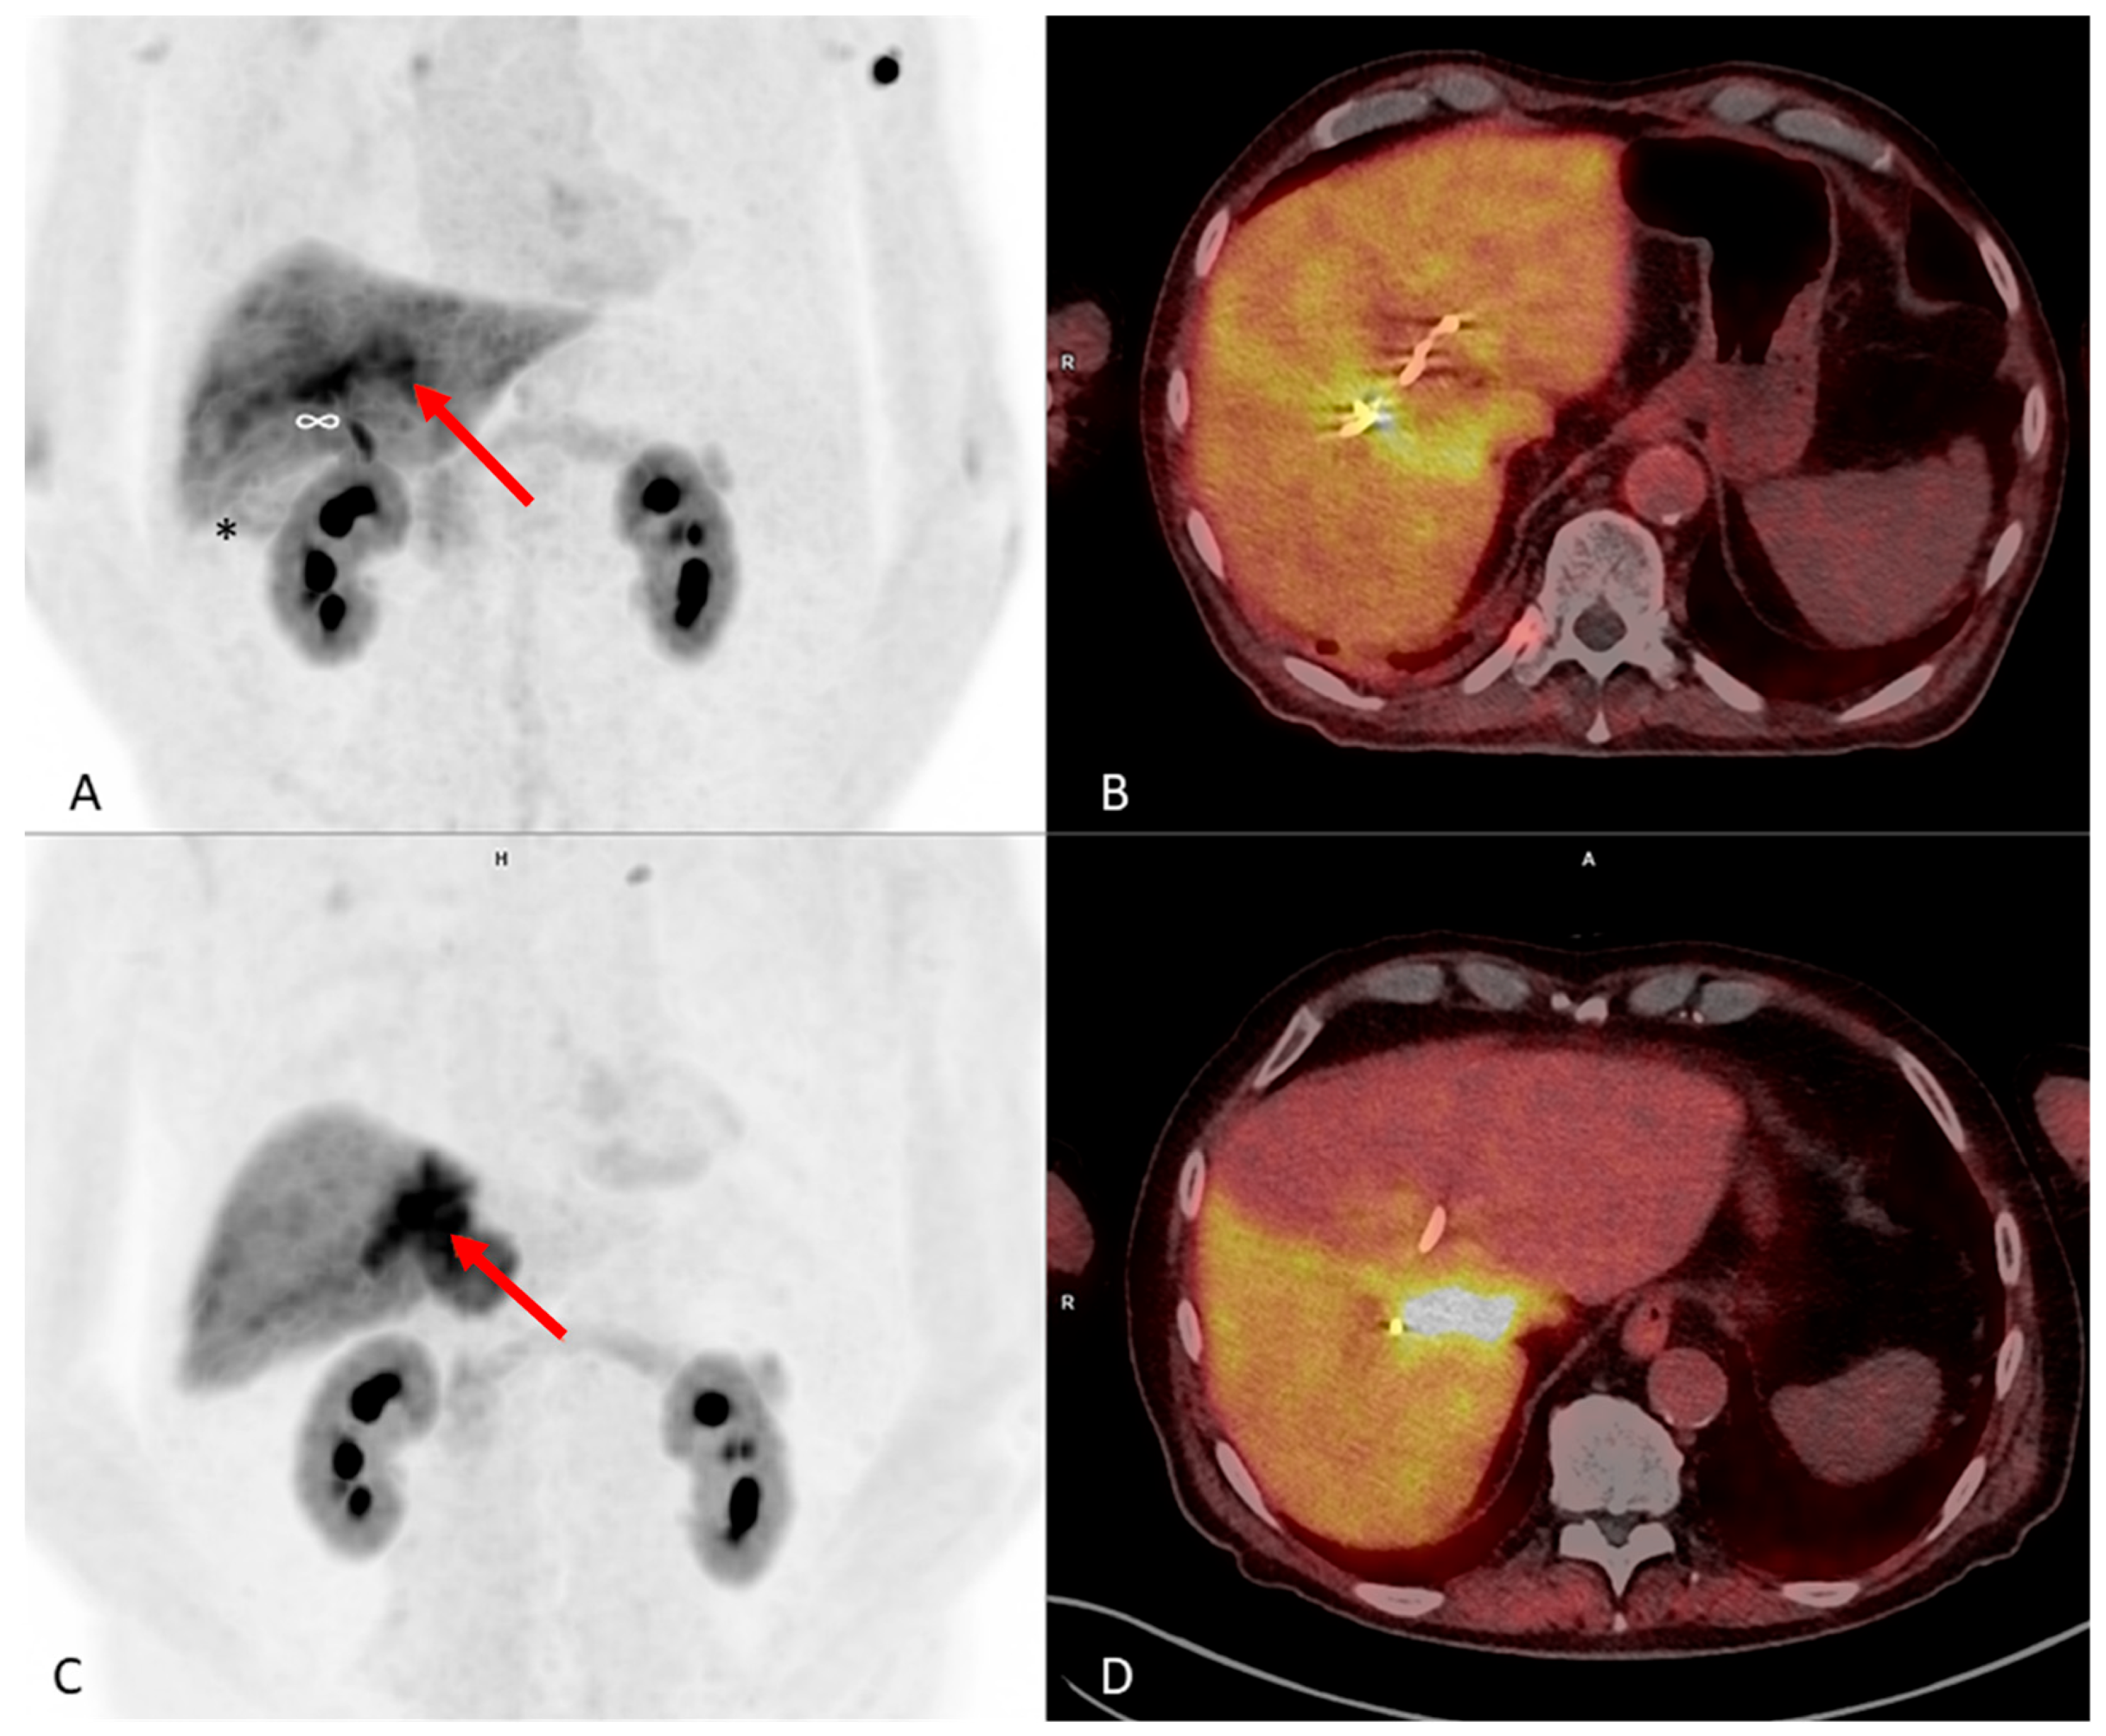

2.3. [68Ga]Ga-FAP-2286-PET/CT Scans and Further Clinical Outcome